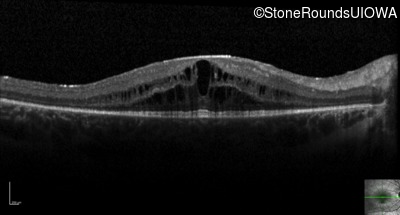

Optical Coherence Tomography - Right - 20/32 -1

Exemplar / OCT Stack